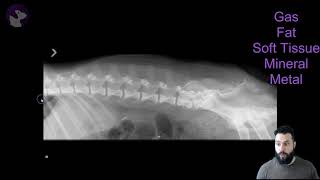

What Are The Radiographic Opacities?

1.041

1:41